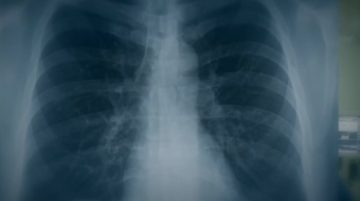

MAREA BRITANIE: Peste 17.000 de decese cauzate de noul coronavirus

Autoritățile sanitare britanice au raportat, marți, alte 828 de decese ale unor persoane spitalizate cu COVID-19.

Bilanțul epidemic a ajuns 17.337 de cazuri mortale în Regatul Unit.

Numărul total de contaminări a urcat la 129.044.

Cifrele publicate zilnic în Marea Britanie nu includ decesele din centrele de îngrijire sau de la domiciliu.